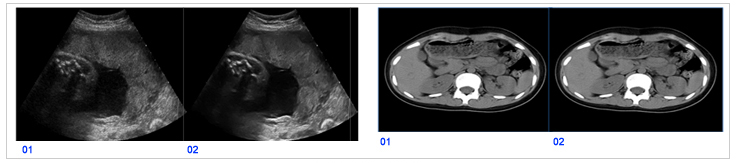

GOP VIEWは,モダリティメーカー対象の超音波,X線静止画・動画像,MRI,CT,歯科等,さまざまな分野でご使用いただける画質改善ソフトウェアです(図4)。現在の画質を向上させるだけでなく,X線分野では低線量で従来線量の画質を実現することも可能です。また,DSP, GPU等幅広いプラットフォームに対応しています。全世界で5万ライセンスを超える実績を誇り,チューニングによって最適かつ独自の画質を実現することが可能です。